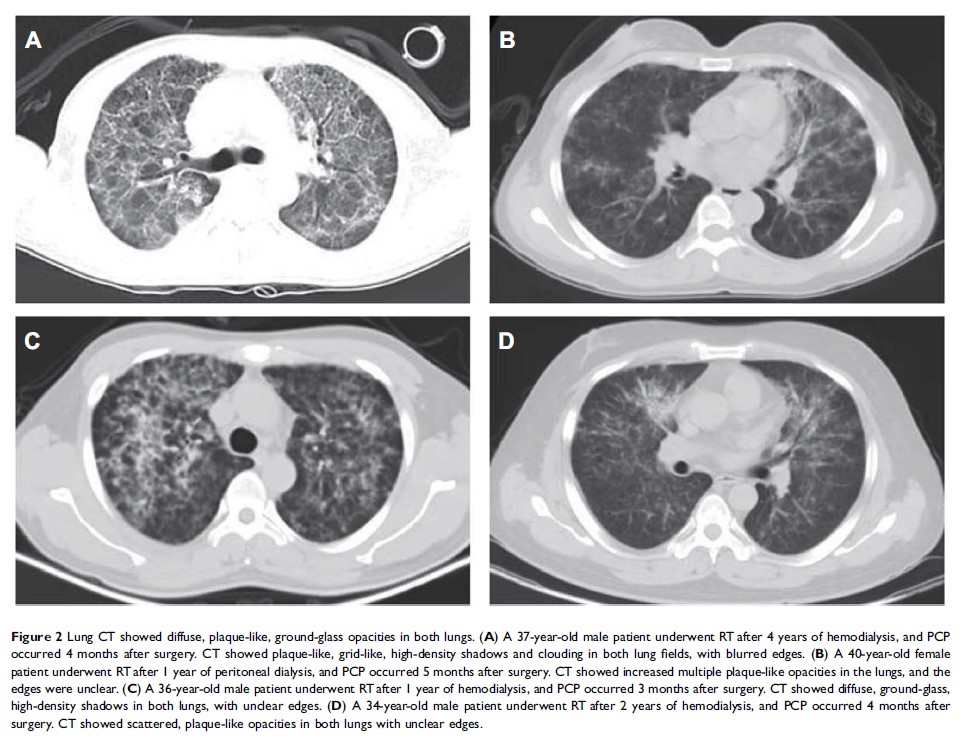

亲体肾移植受者 PCP 临床特点分析